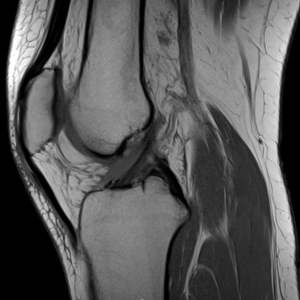

Det är bra att ha en rutin för hur man läser röntgenbilder generellt, även för MR-bilder. Ett exempel för knä kan vara så här:

Identifiera vilket som är lateralt (där man ser fibula). Börja laterala och gå mot medialt

Bläddra från ventralt till dorsalt, tillbaka till ventralt, upprepa vid behov.

Superiort till inferiort